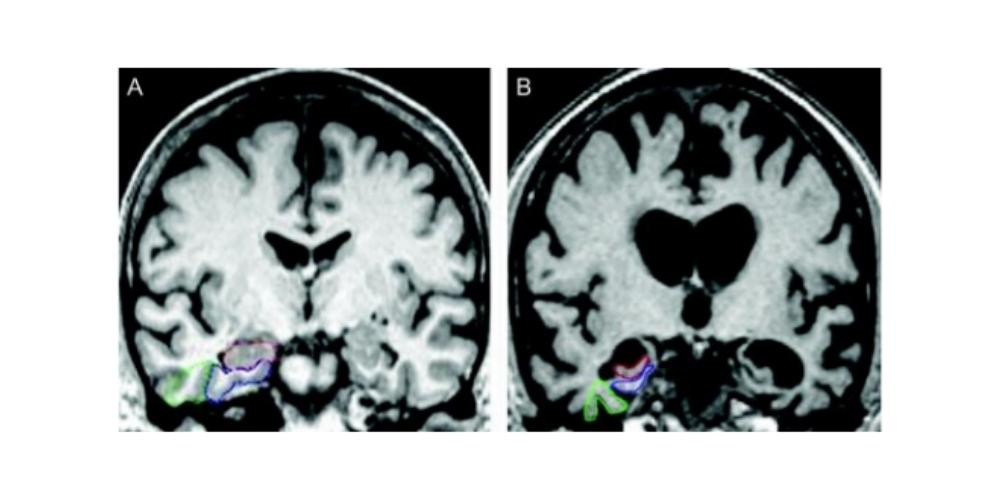

Researchers performed a post-treatment MRI on the brain of each participant. The MRI revealed that the blood-brain barrier opened within the target areas after the ultrasound treatment and then closed after 24 hours.

The authors went on to explain the process behind the new ultrasound treatment. LIFU consists of placing a helmet over the patient’s head after they are positioned in the MRI scanner. This helmet is then equipped with more than a thousand separate ultrasound transducers pointing in different directions. Each transducer delivers sound waves which are directed to a target area of the brain. During the procedure, patients are given an ultrasound contrast agent intravenously that is made up of microbubbles. These go changing in size and shape as the ultrasound is applied. Dr. Mehta said this oscillation results in transient loosening of the blood-brain barrier, which they documented using gadolinium contrast enhanced MRI.